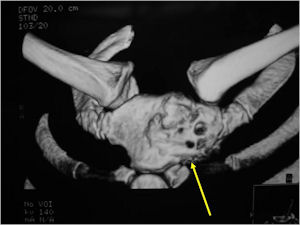

CT Scan:

- More useful for detecting mineralization and evaluating extent of bone destruction than plain X-ray

- There may be expansion of bone, cortical thinning and cortical breakthrough. A soft tissue mass may accompany this lesion but the soft tissue component is usually contained by the periosteum.

- The periosteum remains intact around the soft tissue component. Might need a CT scan to detect the subtle calcification (Egg Shell Rim of Calcification) associated with an intact periosteal reaction